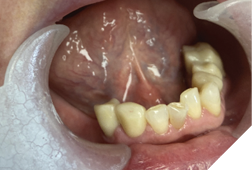

A 72-year-old Caucasian female presented with long-standing TMJ discomfort and missing teeth. She was diagnosed with partial mandibular edentulism (missing 37, 45, 46, 47), generalized attrition, and arthrogenic TMD due to posterior bite collapse. Her periodontal condition was stable.

After informed consent, Phase I began with delivery of a Gelb appliance (Fig. 3ABC), which was adjusted periodically until achieving the treatment VDO. Phase II involved stabilization at this VDO. Teeth 36, 35, 43, and 44 were prepared simultaneously, and impressions (Henry Schein VP MIX) and bite registration (Kopy ultra-fast VPS) were taken using the palatal jig.